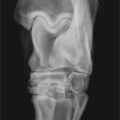

Spatt i begge bakbein – Veterinæren svarer

Hva vil det si at en hest har spatt, og kan man ri en hest med denne lidelsen? Og hva slags risiko er det å kjøpe en hest med spatt?